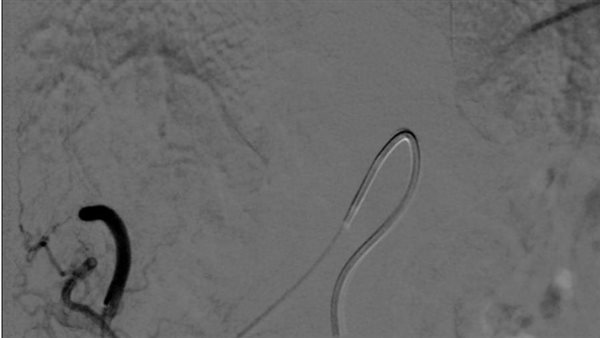

وأشار الدكتور عمرو الدخاخنى المدير التنفيذي لمستشفيات بنها الجامعية، أن هذة العمليه الأولى من نوعها يتم علاجها من خلال جهاز الأشعة المقطعيه 128 متعدد المقاطع حيث تم علاج الورم من خلال قسطره بالشريان الكبدي للفص الأيسر من الكبد ونجاح عمليه الحقن التي تظهر اختفاء الاوعيه الدمويه المغذيةللورم.

فى سياق آخر نجح فريق طبي بوحدة القسطرة التداخلية الطرفية بمستشفيات جامعة بنها بإشراف الدكتور عمرو الدخاخنى المدير التنفيذي لمستشفيات بنها الجامعية، في تركيب دعامة مغطاة لمريضة عمرها 61 عاما، تعانى من تمدد بالشريان الأورطى البطينى ذات حجم كبير وبه تسريب دموي.

وأوضحت المستشفى، في بيان لها، أنه جرى استقبال المريضة وتعاني من تمدد بالشريان الأورطى البطينى ذات حجم كبير وبه تسريب دموي، وجرى عمل الأشعة والتحاليل اللازمة لها والتشخيص المبدئي لها، حيث تم التشخيص بواسطة جهاز الأشعة المقطعية 128 متعدد المقاطع الخاص بالشرايين التاجية بقسم الأشعة بمستشفيات جامعة بنها، وتجهيز غرفة العمليات، وبعد إجراء عملية القسطرة المريضة وهي الآن فى حالة صحية جيدة.